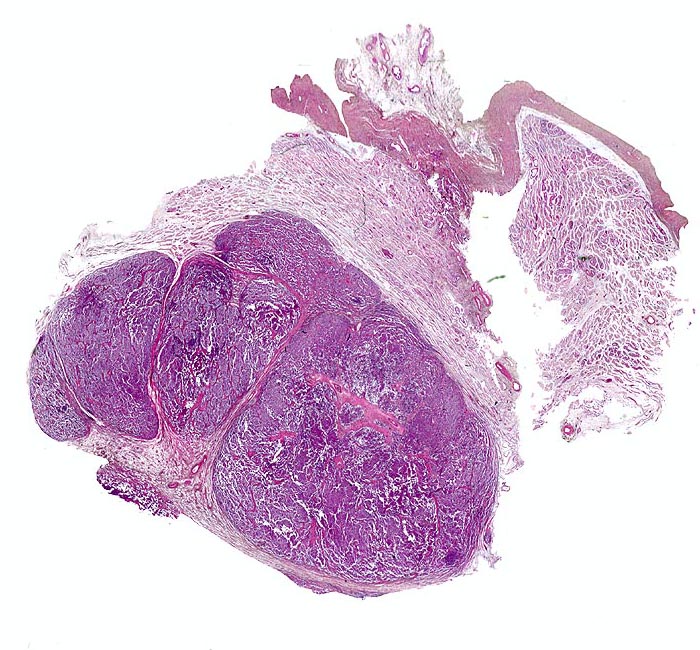

PathoPic ID 4677 - Seminom des Hodens

Seminom des Hodens

maligner Tumor

Hoden

Genitalorgane, männlich

Lobulierter zellreicher

Tumor mit scharfer Begrenzung.

Tunica albuginea.

Makroskopisch aus mehreren Knoten bestehender weisser Tumor von 2cm Durchmesser.

Der Patient suchte den Arzt wegen einer schmerzlosen Hodenvergrösserung auf.

Histologie

Scan

36

männlich